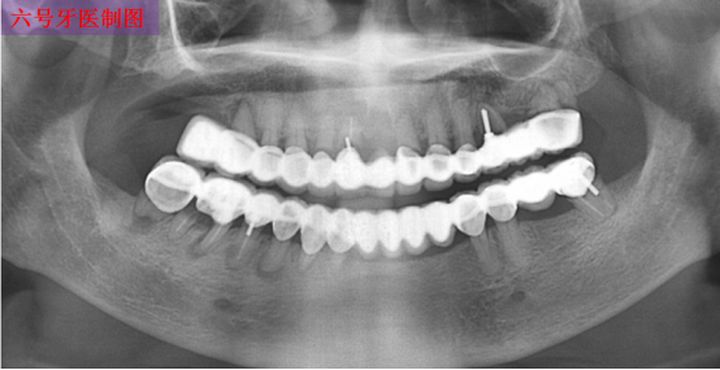

(上图为全口28颗烤瓷联冠,上下各14颗)

“跨江大桥”般的联冠,因为涉及基牙数目多,本身制作的难度就偏大,难度大意味着失败率高,为了寻找多颗牙齿之间的共同就位道,可能会出现过多的磨除基牙,进而导致牙齿敏感,意外露髓,丧失良好的固位形,失去肩台……

(下颌四个单位的联冠,红圈处基牙龋坏)

一损俱损,多颗基牙连在一起组成的联冠,一旦其中一颗牙齿出现了问题,那这一排烤瓷牙可能都会跟着遭殃,面临着被拆除的风险。